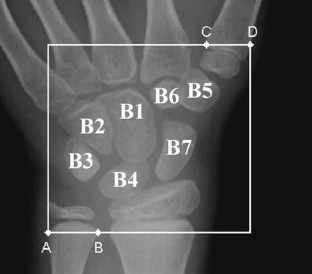

There are two well-known methods to assess bone age, the Greulich–Pyle method and the Tanner–Whitehouse method, which both utilize the hand radiogram to make bone-age assessment to assist medical doctors to identify the growth status of children. Basically, the morphology of bones could be evaluated to quantitatively describe the maturity. The study extracted the morphology of carpal bones and applied the fuzzy theory with principle component analysis to estimate the maturity of skeleton. Five geometric features of the carpals were extracted including the bone area, the area ratio, and the bone contour of the carpals. In order to analyze these features, the principle component analysis and the statistical correlation combined with three different types of procedure were used to construct a growth model of carpals. Eventually, the results of the three types of procedure with fuzzy rules can construct a bone-age assessment system to identify the maturity of children. The study shows that the proposed model based on fuzzy rule has an accuracy rate above 89% in Type-I and II, and above 87% in Type-III within a tolerance of 1.5 years.